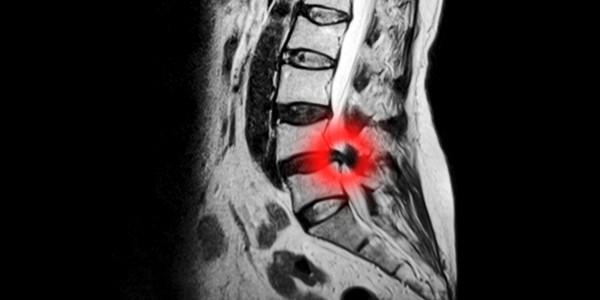

Herniated or Bulging Discs

Damage to the disc tissue between each vertebrae can cause it to change shape.  This can be a mild bulging or a herniation of disc tissue, causing it to press on the spinal canal and /or nerves, causing Stenosis.